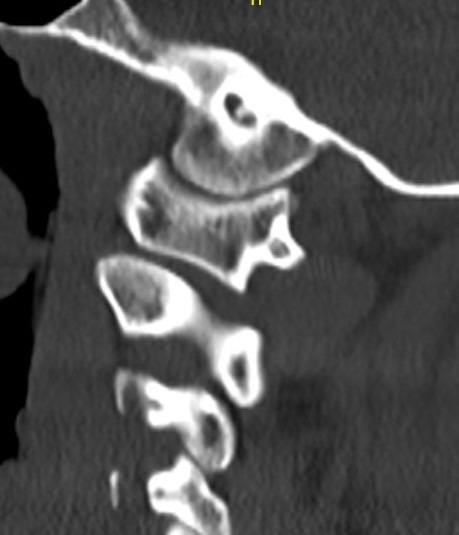

CT Scan

Atlanto-axial rotatory instability

Classification Fielding & Hawkins

| Type I |

Unilateral facet subluxation / dislocation ADI < 3 mm |

Transverse ligament intact | Most common |

| Type II |

Unilateral facet subluxation / dislocation Anterior displacement of the atlas by 3–5 mm ADI 3 - 5 mm |

Transverse ligament injury | |

| Type III |

Bilateral facet subluxation / dislocation Anterior displacement of atlas by more than 5 mm ADI > 5 mm |

Alar and tranverse ligament deficient Both lateral masses displaced anteriorly |

|

| Type IV | Posterior displacement of atlas | Ondontoid process deficient or fractured |

Rare Highest risk of neurological injury |